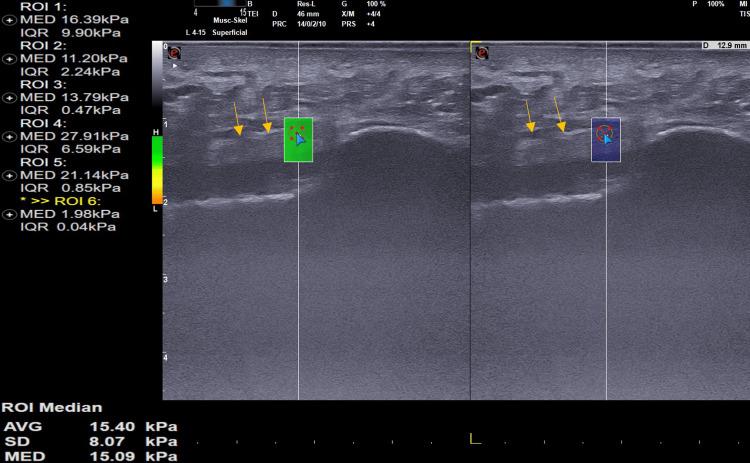

The study found no significant difference in the plantar fascia thickness between affected and unaffected sides, with a mean thickness of 4.3±0.8mm and 5.1±0.6mm, respectively. Shear wave velocity (SWV) was lower on the affected side, indicating reduced stiffness compared to the unaffected side. The Spearman rank test revealed strong direct correlations between SWV and both the VAS and HF-AOFAS scores on the affected side.

研究发现患侧与未患侧足底筋膜厚度无显著差异,平均厚度分别为4.3±0.8mm和5.1±0.6mm。患侧的剪切波速度(SWV)较低,表明与未患侧相比刚度降低。Spearman秩相关检验显示,患侧SWV与VAS评分和HF - AOFAS评分之间存在强正相关。